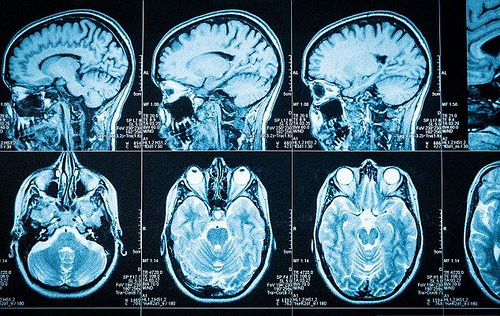

进行了两次实验。在第一次实验中,37名学生表现出中性和令人不安的样子,然后被要求以第一人和第三人的方式在脑中对它们做出反应,透过脑波图(electroencephalography,EEG)来监视他们的大脑活动。

脑波图读数显示,当看到令人不安的样子时,当时使用第三人的方法,大脑中的情绪活动会降得非常快,不到一秒钟。

第二项实验涉及到52名志愿者,被要求反省过去痛苦的经历,再次使用第一人和第三人的语言来自我交谈。这次使用功能性的核磁共振(functional magnetic resonance imaging,fMRI)来监视大脑活动。

研究人员发现,第三人的自我交谈会导致大脑连结到涉及个人痛苦情绪区域的活动较少,这个区域在前额叶皮质(prefrontal cortex)内侧附近。